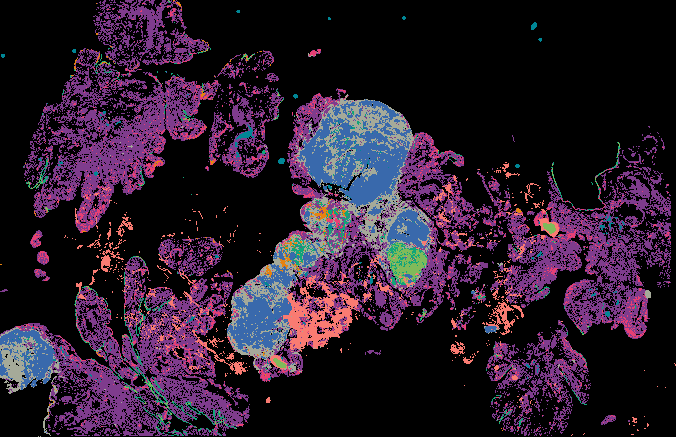

Serous Tubal Intraepithelial Carcinoma (STIC) with BRCA2 Mutation (LSP18251) from 'Multimodal Spatial Profiling Reveals Immune Suppression and Microenvironment Remodeling in Fallopian Tube Precursors to High-Grade Serous Ovarian Carcinoma'.